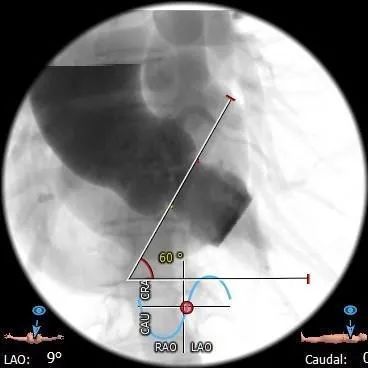

•主动脉瓣水平夹角约60°,横位心,主动脉弓宽度角度可,弓顶部散在附壁钙化

主动脉根部造影

输送器顺利过弓、跨瓣

瓣膜标准位定位